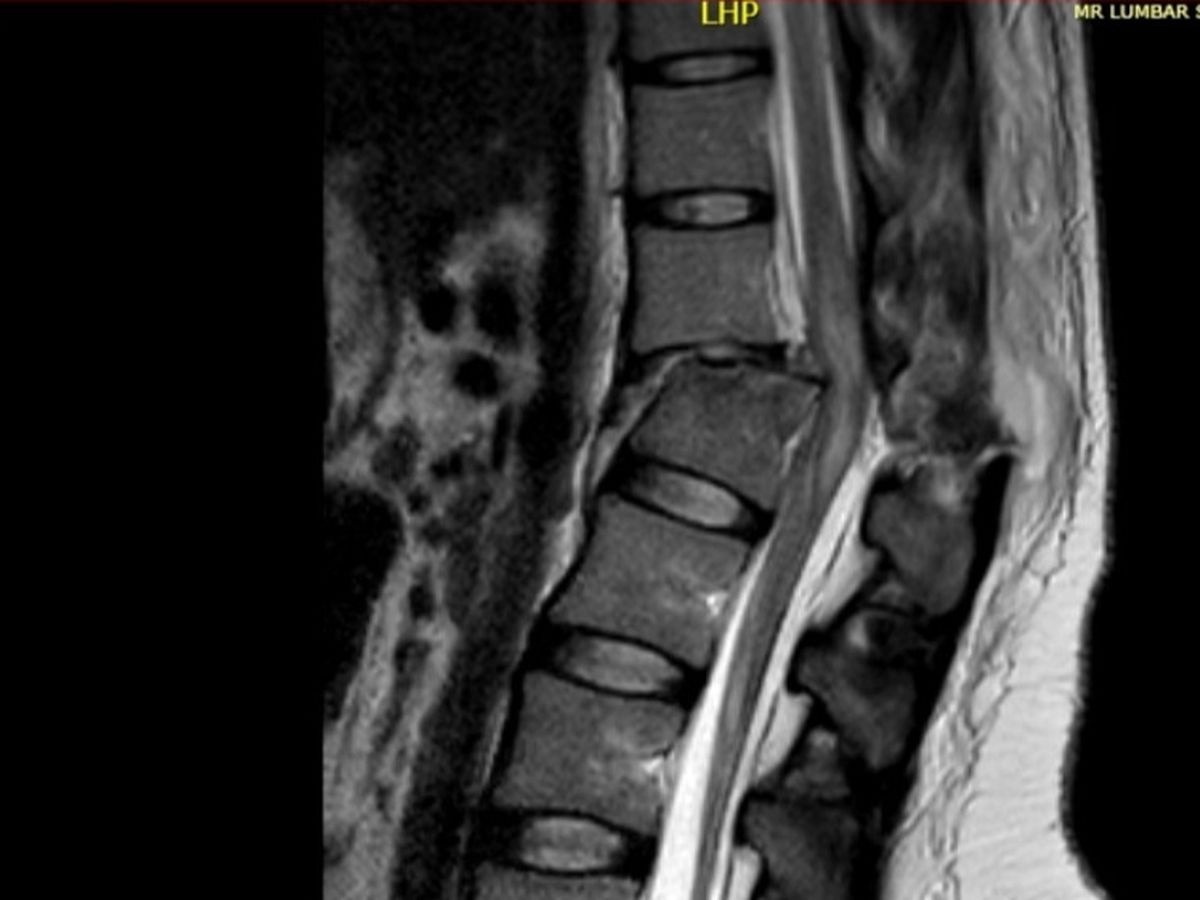

After arriving at the trauma bay and being asked a million and one questions by doctors in order for them to assess me, I'm rushed into surgery for a spinal fusion. I wake up and still cannot move my lower half. Doctors tell me I shattered my L1 and even though it was an incomplete injury, they don't know how much I'll get back and if I will ever walk again. The rest is history. I spent over a month in the hospital and fought like hell in therapy to make advances, and that I did. I started to get some motion and sensation in my legs back. I even got to the point of being able to stand up and push my legs to make steps with a bilateral walker and some assistance. Now there isn't a question in my mind of if I will walk again, it's a matter of when. I lost a lot that day, but I gained a fire inside of me I had never felt before. There's no giving up or quitting. There's only the moment I visit all the staff that took care of me, and I walk through the same doors I rolled out of a wheelchair in.